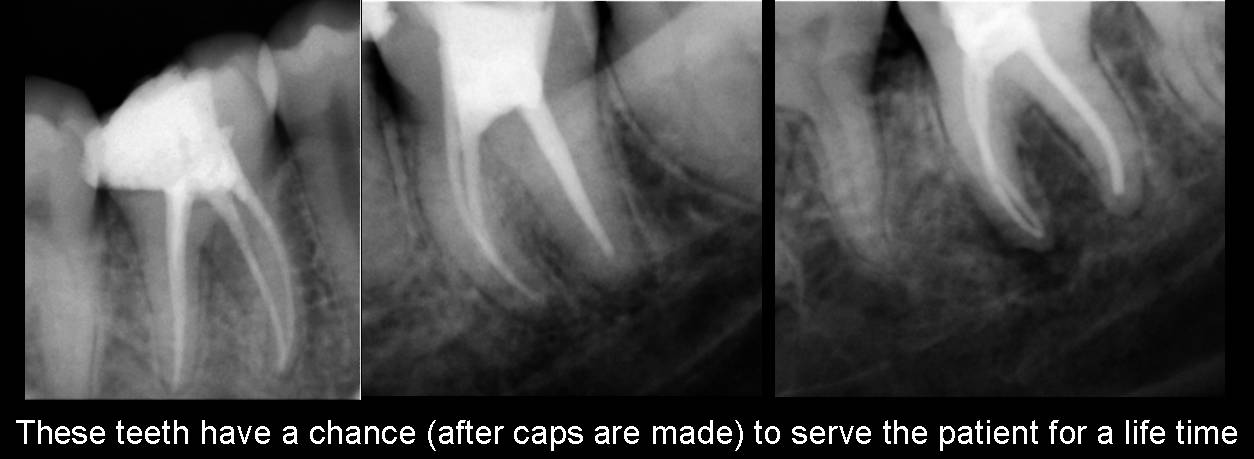

Since

all the root canals are curved, these two objectives are fulfilled only with

extremely flexible instruments. By using these instruments, we are saving the

tooth for a life time, or for at least many many years. This type of instruments,

I started my endodontic work more

than three decades back. I have seen many patients retain root canal treated

teeth (treated just once) till their death. Now when I look around, the re-

root canal treatments are on an all time high. You can also check among your

relatives and friends how many of them had to get re- root canal treatments

done recently and how many who got it done once 20- 25 years back are still retaining the tooth.